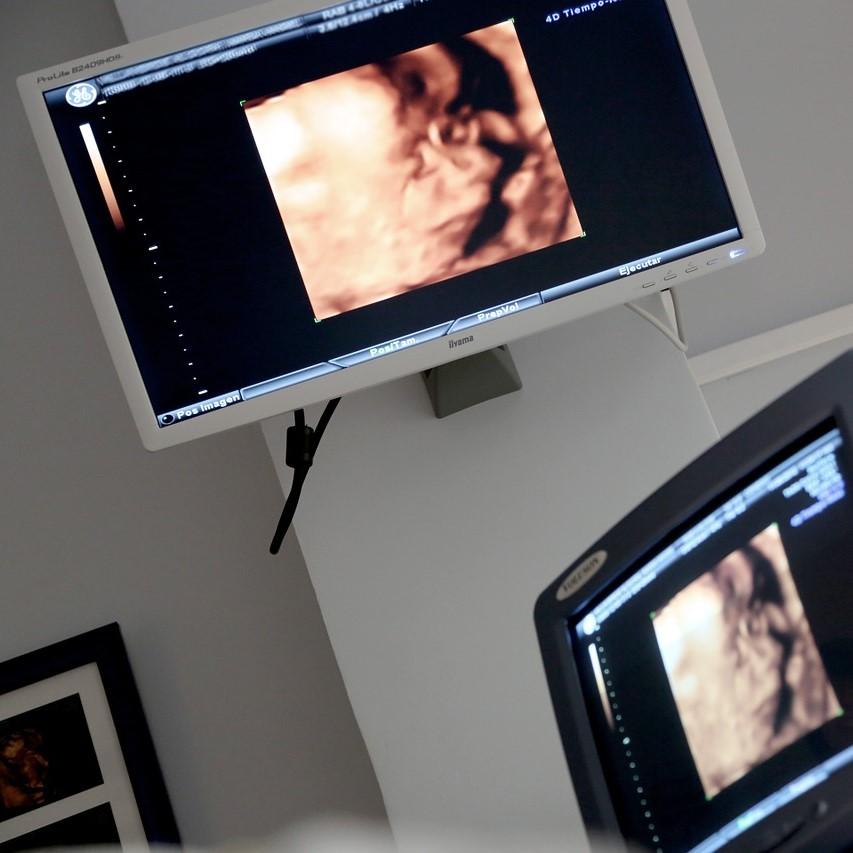

La ecografía es un sistema para obtener imágenes a través de los ecos de los ultrasonidos dirigidos a un cuerpo u objeto. Se trata de ondas sonoras de alta frecuencia que se dirigen al organismo del estudio y al recibir la gran onda de sonido emite un eco. A través del transductor se recoge la información y un ordenador lo convierte en una imagen definida en una pantalla. Para que funcione correctamente se suele añadir un gel sobre la piel que facilita la transmisión de ondas.